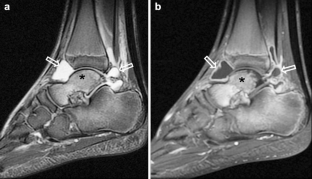

Synovium is the thin membranous lining of a joint. It produces synovial fluid, which lubricates and nourishes the cartilage and bone in the joint capsule. Synovial diseases in children can be classified as normal structures as potential sources of pathology (synovial folds: plicae, infrapatellar fat pad clefts), noninfectious synovial proliferation (juvenile idiopathic arthritis, hemophilic arthropathy, lipoma arborescens, synovial osteochondromatosis, pigmented villonodular synovitis, reactive synovitis), infectious synovial proliferation (pyogenic arthritis, tuberculous arthritis), deposition disease (gouty arthropathy), vascular malformation, malignancy (metastasis) and intra-/periarticular cysts and cyst-like structures. Other intra-articular neoplasms, such as intra-articular synovial sarcoma, can mimic synovial disease in children.